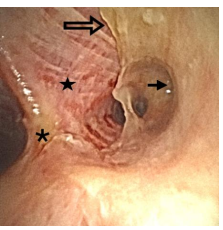

A follow up chest x-ray on Day 17 showed increasing atelectasis (Figure 2) and repeated bronchoscopies the next days turned out to be of utmost importance. Her airways were completely covered with a continuous membranous pale layer, starting along the tracheal tube, reaching down into the bronchial segments (3rd generation bronchi) narrowing the inner lumen significantly. The membranes completely covered the entrance to the left upper lobe, while the right upper lobe bronchus was left with a small remaining lumen (Figure 3).

Figure 3: The right main bronchus with the carina (asterisk) to the left as seen through the bronchoscope. The membrane (open arrow) was easily detachable by forceps and revealed a raw, inflamed bronchial wall underneath (star). The bronchial orifice to the upper right lobe was significantly narrowed (arrow).

With a combination of flushing with saline and use of forceps, the membranous layers were successively removed down to the segmental level. The membranes were easily detached in large pieces from the wall. Due to their large size, the individual pieces had to be removed mechanically by retracting the bronchoscope with the forceps in place. Bronchoscopy had to be repeated over three consecutive days before the bronchial lumens were found to be satisfactorily open. The removal exposed a large wound surface, however, there were hardly any signs of reappearance of the membranes. Microbial tests of bronchial fluid demonstrated growth of P. aeruginosa despite antibiotic coverage with meropenem from the time of intubation. No Aspergillus spp. or other common respiratory pathogens were found in our patient. Due to deteriorating renal function, continuous renal replacement therapy (CRRT) was started on Day 18. On Day 20, the patient developed a generalized vesicular rash. Qualitative PCR test of fluid from vesicles and peripheral blood was positive for VZV DNA (Altona Realstar GmbH, Hamburg, Germany). New testing on blood samples taken before her transplantation came up positive for VZV IgG, indicating that the current VZV infection was caused by reactivation. Retrospective blood analyses also demonstrated VZV DNA one day ahead of the surgical fenestration of her lymphocele, and repeated chest x-rays showed progressive, scattered nodular and reticular consolidations in both lungs compatible with VZV pneumonia (Figure 1). Upon reassessment, the bronchial lavage samples collected at the time of intubation also revealed the presence of VZV DNA in the patient's airways. Intravenous acyclovir was started on Day 20, and considering her critical state, immunosuppression and prolonged hospitalization, linezolid and anidulafungin were empirically added. Regarding her immunosuppression, the dosages of tacrolimus and MMF were held stable during her intensive care course, and additional corticosteroids were initially added, based on the suspected aspiration pneumonitis. However, after the findings of VZV, the methylprednisolone dosage was lowered to baseline level of 15 mg. After a distinct increase in plasma levels of tacrolimus on Day 21, the dosages of tacrolimus and MMF were both reduced. From Day 22 her respiratory failure gradually improved, sedatives could be reduced, and linezolid and CRRT were terminated on Day 25. Due to an unsuccessful extubation on Day 27, she was tracheostomized to ease further weaning from the ventilator. Her vesicular rash had developed into crusty lesions, but blood tests showed persisting VZV viremia. Antiviral treatment was therefore continued, while antibiotics and antifungal treatment were discontinued. The further weaning of the ventilator was complicated by new infections and recurring need of broad-spectrum antibiotics. On Day 49, after 34 days of mechanical ventilation, she could finally be decannulated and transferred to a hospital ward for rehabilitation with a well-functioning kidney graft. VZV DNA was detected in her blood until Day 60. She was discharged from the hospital on Day 118, still in need of a nasogastric tube feeding and further rehabilitation.